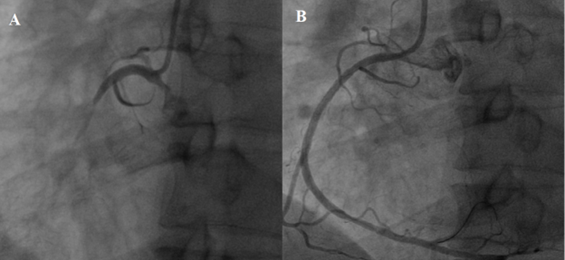

Hình ảnh chụp động mạch vành của bệnh nhân H.Đ.H cho thấy tắc hoàn toàn động mạch vành phải (A) và hình ảnh tái thông hoàn toàn sau nong bóng và đặt stent (B).

Bệnh nhân H.Đ.H (nam, 51 tuổi, ngụ tại TT.Núi Thành, Quảng Nam), nhập viện cấp cứu tại Bệnh viện trong tình trạng đau thượng vị dữ dội, vã mỗ hôi, chóng mặt, buồn nôn, huyết áp tụt 70/40 mmHg, SpO2 giảm 85%, nhịp tim nhanh 145 lần/phút. Kết quả điện tâm đồ và các xét nghiệm cận lâm sàng cho thấy bệnh nhân bị nhồi máu cơ tim cấp ST chênh lên, biến chứng choáng tim và rối loạn nhịp nhanh. Bệnh nhân nhanh chóng được hội chẩn chụp động mạch vành cấp cứu kết hợp dùng thuốc vận mạch để duy trì huyết áp và các thuốc cấp cứu khác. Kết quả chụp động mạch vành cho thấy tắc hoàn toàn động mạch vành phải, tiên lượng rất nặng, nguy cơ tử vong cao.

Bệnh nhân được can thiệp cấp cứu, nong bóng và đặt stent động mạch vành (P). Tổng thời gian thủ thuật, gồm chuẩn bị, chụp, can thiệp nong và đặt stent động mạch vành cấp cứu bệnh nhân là 19 phút. Kết quả sau can thiệp cho kết quả tốt, theo dõi liên tục cho thấy bệnh nhân giảm nhanh triệu chứng, ổn định huyết áp 130/80 mmHg, nhịp tim về bình thường 85 lần/phút, dừng thuốc vận mạch sau can thiệp 6 giờ. Bệnh nhân xuất viện sau 5 ngày trong tình trạng sức khỏe tốt, hoàn toàn không còn triệu chứng.